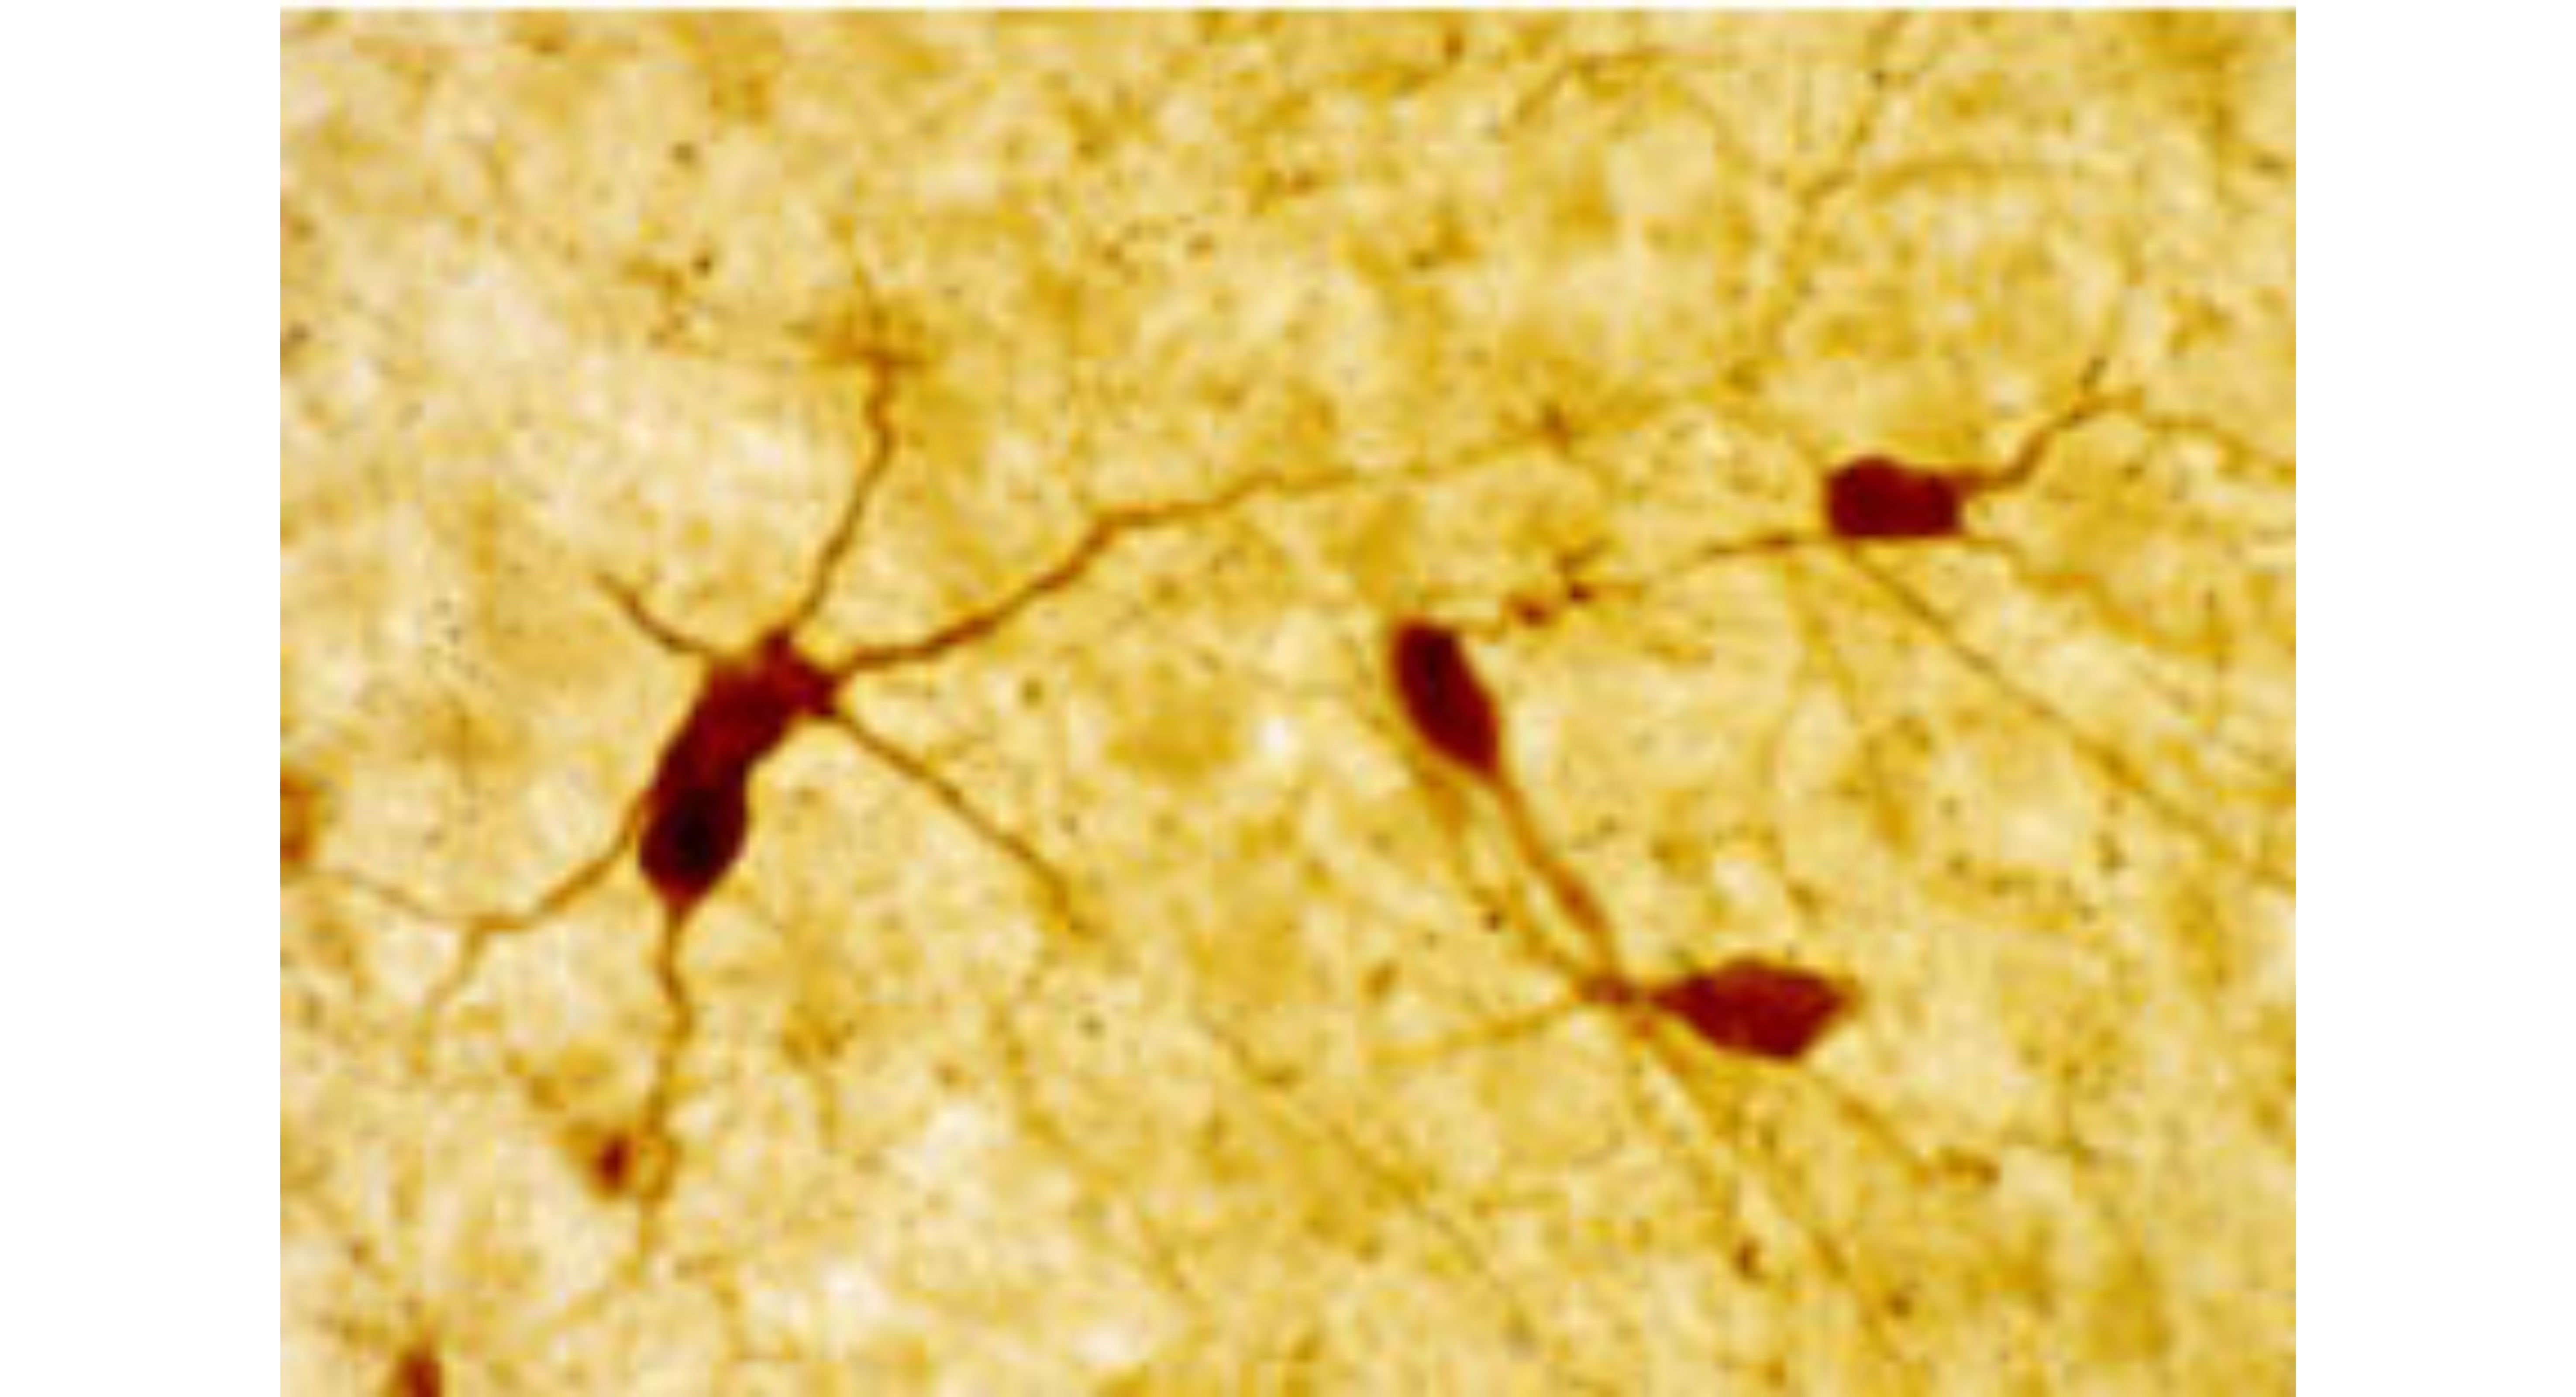

ImmunoStar原装阿尔茨海默病(AD)研究系列抗体

ImmunoStar原装阿尔茨海默病(AD)研究系列抗体,助力神经科学科研突破,超8000+ SCI文献广泛引用,高特异性,批间稳定. -